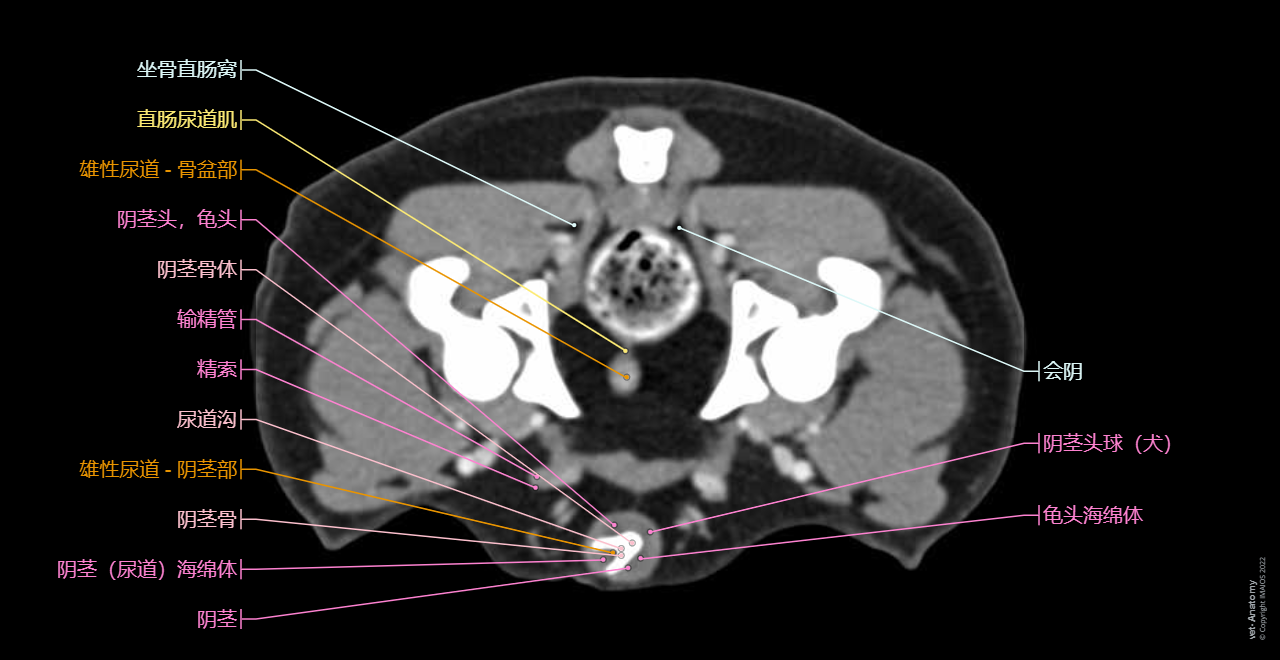

在vet-Anatomy动物图集的此模块中,计算机断层扫描(CT)显示了标有解剖结构的犬科腹腔和骨盆横截面,并用3D图像显示犬科腹部。

CT图像存在3个平面方向(横向,矢状和背侧),并且使用两种对照方式(软组织/血管和骨骼)展现。本模块的末尾提供其他3D解剖图像,便于进一步了解犬科总体解剖结构,展示了骨骼、内脏(肝脏、脾脏、胰腺、消化道)、泌尿生殖系统、动脉、全身静脉系统(主要是尾腔静脉及其分支)、门静脉系统、肌肉和表面解剖的三维容积透视图。

关于解剖,作者给出以下说明:

• 由于对该犬进行了阉割手术,因此没有睾丸和阴囊,输精管也因此萎缩。

• 在CT中无法直接观察到某些结构,例如神经或腹膜褶,它们的走向和位置是根据动脉或其他相邻结构中估测得出。

Dog - 3D - Urogenital system: Penis, Penile bone [Baculum], Urinary bladder, Male urethra, Male genital organs